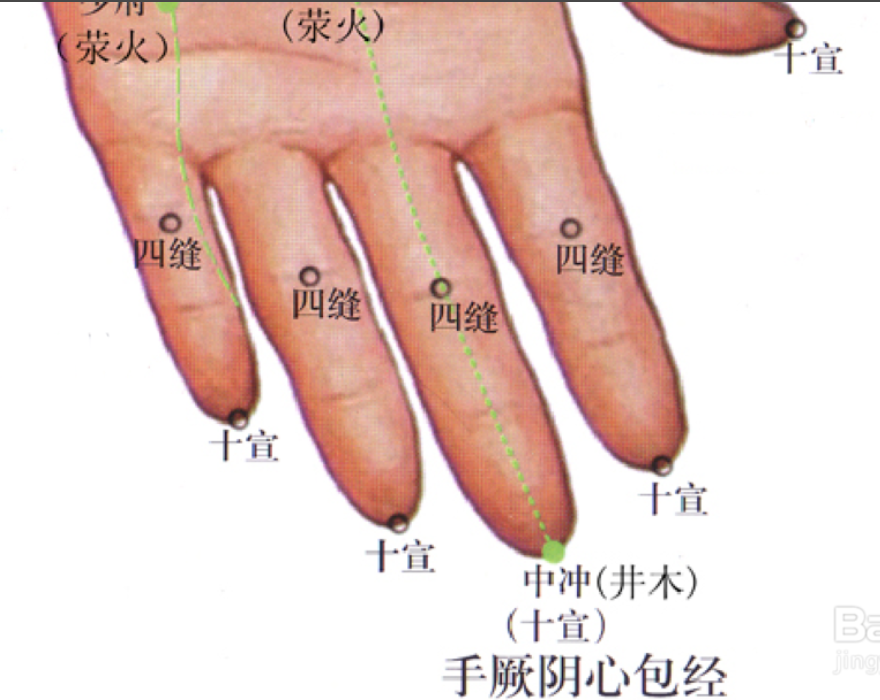

四缝

【定位】 在第 2 至第 5 指掌侧,近端指关节的中央,一手 4 穴,左右共 8 穴(图 10-36)。

【主治】 小儿疳积,百日咳。

【刺灸法】 点刺出血或挤出少许黄色透明黏液。

十宣

【定位】 在手十指尖端,距指甲游离缘 0.1 寸(指寸),左右共 10 穴(图10-36)。

【主治】 昏迷,癫痫,高热、咽喉肿痛。

【刺灸法】 浅刺 0.1 ~ 0.2 寸,或点刺出血。